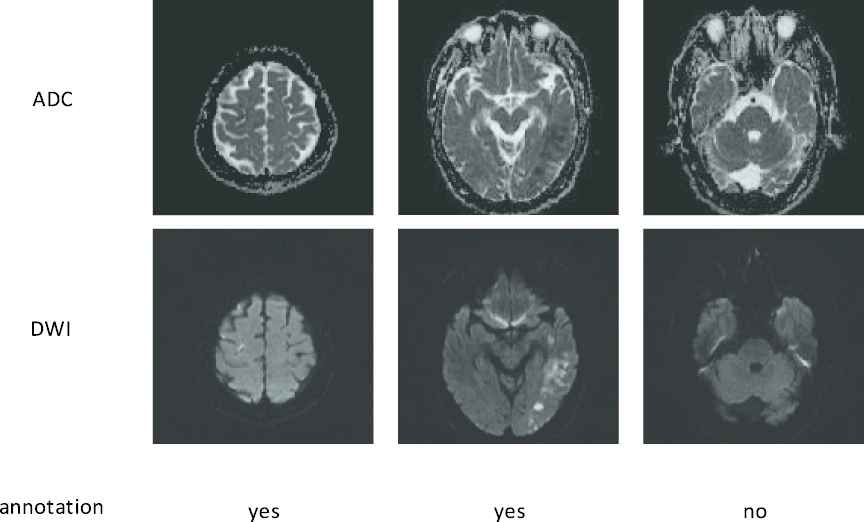

In diagnosing of ischemic strokes, magnetic resonance imaging (MRI) serves as the modality of choice for clinical evaluation. The diffusion-weighted images (DWIs) and the apparent diffusion coefficient (ADC) maps derived from multiple DWIs with different b-values have been shown to be sensitive in diagnosing acute ischemic stroke (AIS). In particular, the AIS lesions appear as hyperintense on the DWIs and hypointense on the ADC maps [3]. Figure 1 presents some examples of AIS lesions. The regions identified by the red arrows are AIS lesions. The regions identified by the yellow arrows, although also shown as hyperintense on the DWIs, are non-lesion regions. In fact, such hyperintensive regions are the magnetic susceptibility artifacts. That is to say, despite that they appear as hyperintense on the DWIs, there is no abnormality on the ADC maps. Therefore, to correctly identify the lesions, it is important to jointly consider both DWIs and ADC maps to extract the semantic information.

Figure 1

Challenge examples in acute ischemic stroke (AIS) segmentation. The first row show apparent diffusion coefficient (ADC) slices and the second row shows their corresponding diffusion-weighted image (DWI) slices. The yellow arrows identify the hyperintense due to magnetic susceptibility artifacts, and the red arrows identify the hyperintense that are true AIS lesions. Best viewed in color.